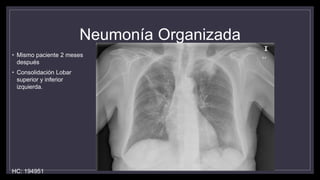

Neumonía Organizada

• Mismo paciente 2 meses

después

• Consolidación Lobar

superior y inferior

izquierda.

HC: 194951